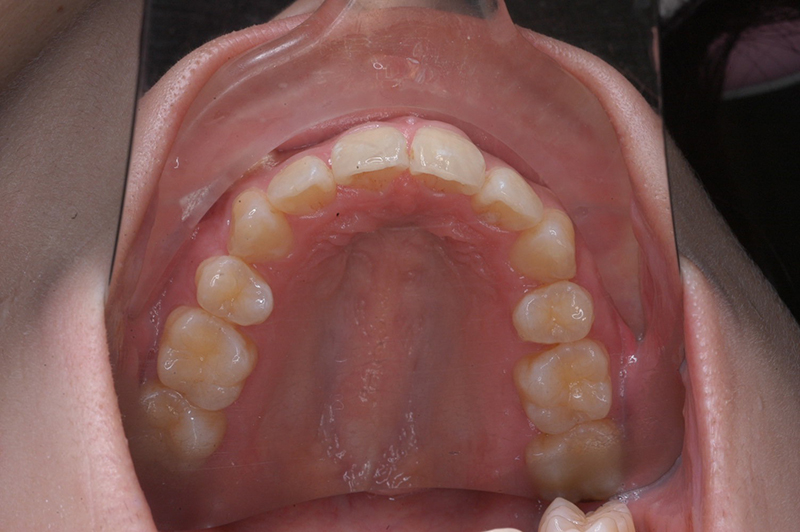

初診時

主訴 口が閉じづらい 診断名 アングルⅠ級上下顎前突症例

初診時年齢 19歳5ヵ月 性別 動的治療期間 26ヵ月

口腔内所見 大臼歯関係はⅠ級。顔面正中に対して上顎正中は一致しており、下顎正中は右側に偏位していた。上下顎前歯は大きく唇側傾斜し、overjetが7.8mmの上突咬合、両突歯列、叢生歯列弓であった。